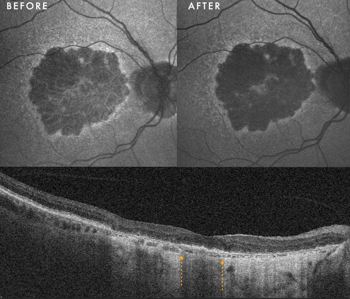

Response to therapy: Following PBM, one eye exhibited a remarkable anatomical response: the PED resolved and flattened, accompanied by a significant restoration of the ellipsoid zone on OCT. Crucially, this occurred without the expected RPE atrophy (See Fig 1 at the top of this article).

This structural success was matched functionally, with BCVA improving from 6/9 to 6/6. In the fellow eye, the PED remained structurally stable, yet she still achieved functional gain, improving from 6/30 to 6/24.